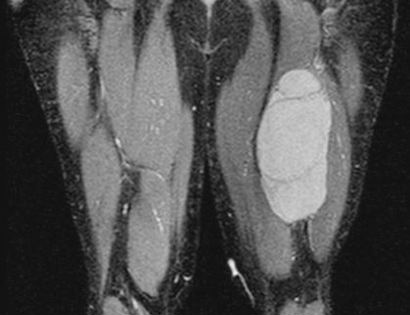

This is an MRI of the hamstrings tumor. The tumor is the brightened part on the right hand side of the thigh in the image seen.